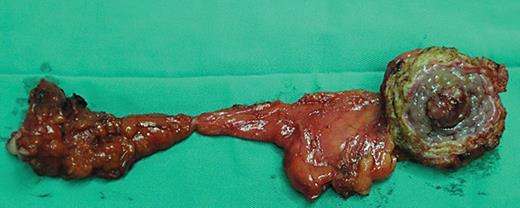

The average size of urachal tumors was 3.9 cm (range: 1.3–8.0 cm, the resected specimen shown in Fig. 2). Of 59 urachal cancers, the tumor was located in the dome of the bladder in 47 cases (76.09%) and at the anterior wall of the bladder in 10 cases (21.74%) (2 cases were multiple tumors). Histologically, 19 cases were adenocarcinoma not otherwise specified (NOS), 19 cases were mucinous adenocarcinoma, 5 cases were adenocarcinoma with mucinous adenocarcinoma, 5 cases were mucinous adenocarcinoma with signet ring cells, and 2 cases showed adenocarcinoma mixed with signet ring cells and mucous cells or enteric differentiation. Only 1 case showed pure signet ring cell subtype, and 5 cases exhibited enteric adenocarcinoma. Two cases were small-cell carcinoma and 1 case was transitional-cell carcinoma with adenomatous metaplasia (shown in Fig. 3a–c). Lymph node invasion was present in 6 patients. The positive surgical margin, defined as tumor cells were seen microscopically at any part of the proximal cut edge of umbilical ureteral or resection margin of bladder, was seen in 2 cases.

The resected specimen of umbilical, urachus, and urachal carcinoma.